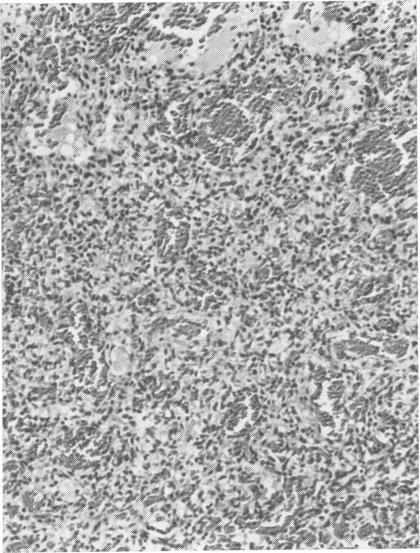

A retrospective study has been carried out on 67 patients harbouring 78 posterior fossa haemangioblastomata. The site, macroscopic nature, and histological features are described, and correlations sought with the degree of erythrocytosis in the peripheral blood. The problems of aetiology are discussed and a single hypothesis advanced.